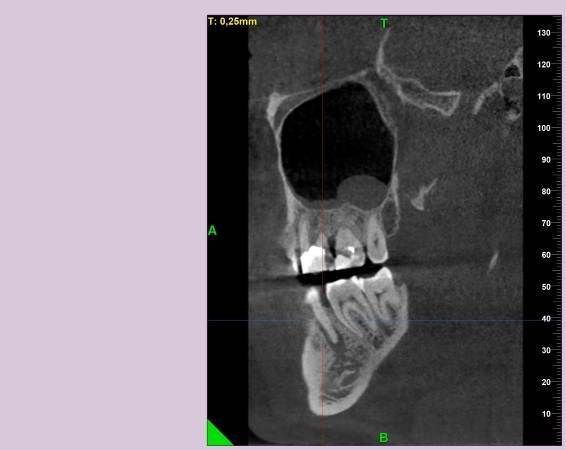

КТ от 04.03.2024

69273_3.jpg.f56a31dc1d8d53085767a9a52915128c.jpg69273_4.jpg.f9ec255bedbdb9fde8159318d3cb1fd9.jpg69273_5.jpg.36a7a942d403dd2eb062e5a4b2b58a52.jpg69273_6.jpg.492d3fbca3808fbdf58c86056b2fe0c3.jpg69273_7.jpg.f9bfdd5d593504dc7bd3710ece18aa4f.jpg69273_8.jpg.853e2342e6f2329a2e89c8939c2aad6f.jpg69273_11.jpg.e495813d50bf007f7165bf5f5dfec4b3.jpg69273_12.jpg.49b3cf66b4dd26b5cd68a91b2684e402.jpg69273_13.jpg.5d61b621b8e8b2c473ad6a8aca42502d.jpg

Добрый день! В данный момент прохожу лечение 46 зуба. Улучшений нет, поэтому возникли сомнения в тактике лечения выбранной моим стоматологом.

Лекарство было извлечено, и каналы запломбированы гуттаперчей. Доктор предупредила, что зуб будет болеть, и прийти я должен после того, как зуб "успокоится", болевые ощущения пропадут. На третий день десна под зубом вспухла, и начала сочиться сукровица. Я решил сделать новое КТ(28.05.2024), и с результатом сходить в другие клиники для консультации. В первой мне сказали, что доктор не должна была начинать лечение, потому, что зуб идет под удаление. Во второй клинике, что попытаться вылечить можно, но изначально были допущены ошибки в лечении, и надо переделывать.

Что-то можно сделать с 46 зубом для сохранения, или он должен быть удален?